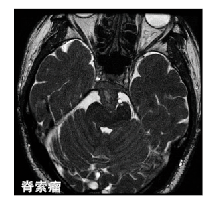

脊索瘤

诊断

NCCN推荐的诊断检查主要包括病史采集、体格检查,对原发肿瘤充分的影像学检查(X线、CT和MRI),对脊柱进行MRI筛查、胸部CT检查、腹部和盆腔CT检查。对于某些特殊病例,可考虑行PET扫描或骨扫描。对骶骨脊索瘤的活检应在背侧进行,而不是腹侧经直肠。

blob.png

治疗

对脊索瘤进行充分外科边界的广泛切除是最佳治疗方案。最近一项针对SEER数据库962例脊索瘤患者资料分析显示,外科手术可显著改善总生存(OS)率。一些研究证实,广泛外科边界是患者无复发生存(RFS)率和OS率的预后影响因素。

放疗与手术结合可提高局部控制率。在一项纳入24例患者的回顾性研究中,术前短期放疗、手术切除、术后小区域大剂量放疗,5年DFS率和局部控制率分别为54%和72%。

除了去分化脊索瘤中的去分化区域,脊索瘤对化疗并不敏感。有研究显示,有几个信号传导通路参与脊索瘤的发生发展过程,包括血小板源性生长因子受体、表皮生长因子受体和mTOR。在一项伊马替尼治疗进展期脊索瘤的研究中,共入组56例患者,70%患者获得疾病稳定;根据RECIST标准确定的临床受益率为64%,中位疾病无进展时间为9个月。

脊索瘤的重要特征是高复发率,据文献报道,40%的局部复发患者会发生远处转移,包括肺、骨、软组织、淋巴结、肝和皮肤。

建议  对于可切除的经典型或软骨样型脊索瘤,肿瘤部位不同,治疗方法也不同,如果在骶骨和可活动脊椎,应进行广泛切除;如果在颅底,进行囊内切除(采用MRI评价切除的充分性),术后可根据情况选择放疗。对于体积较大的间室外肿瘤或外科边界为阳性的患者可考虑行放疗。对于肉眼切缘为阳性的病例或者囊内切除的病例,术后给予放疗可改善局部控制,并提高DFS率。不管部位在哪,对于不能切除的脊索瘤,主要治疗方法均是放疗。对于去分化脊索瘤,可参考NCCN软组织肉瘤进行处理。

对进展的脊索瘤进行手术治疗,可辅助放疗或药物治疗。NCCN推荐的药物包括伊马替尼、顺铂、雷帕霉素、埃罗替尼、西妥昔单抗和舒尼替尼。对于复发的EGFR阳性脊索瘤,将拉帕替尼也列为可选择药物。2013年时曾将西妥昔单抗作为推荐药物,但2014年又将其删除。